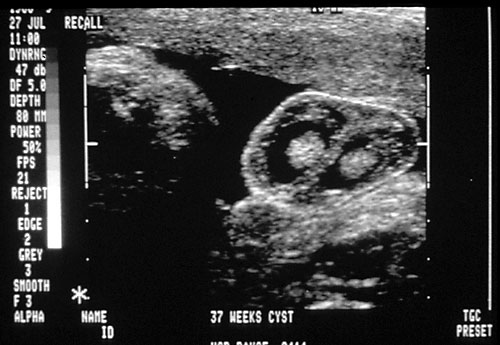

Normal male genitalia (1). Normal female genitalia (2). Bilateral fetal scrotal hydroceles in utero (normal variant) (3).